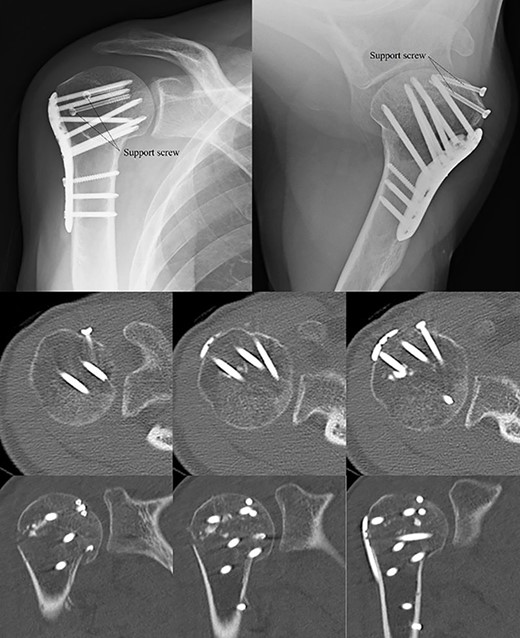

Postoperative radiographic and CT evaluations showed reduced fractures on the humeral head and surgical neck (Fig. 7). At 24 months of postoperative follow-up, radiographic and CT evaluations showed no signs of osteoarthritis or reimpression (Fig. 8). Two years after the primary surgery, we performed implant removal at the patient’s request (Fig. 9). When performing implant removal, we additionally performed a second-look evaluation with arthroscopy to assess the degree of healing in the joint. We noted no impression or exposure of cartilage callus on either side of the humeral head or glenoid (Fig. 10).

Postoperative X-ray and CT scan showing sustained anatomical reconstruction of articular surfaces and no signs of osteoarthritis.

Two years later, pre-implant removal CT showed that the reduction in the depressed surface had been maintained with no obvious arthritic changes.